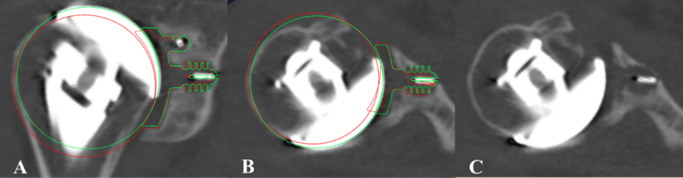

Imaging Arthroplasty

The Arthroplasty Research program focuses on identifying the demographic, disease-related, and surgical factors associated with short- and longer-term clinical outcomes following joint arthroplasty of the hip, knee, and shoulder, including potentially modifiable factors.Our aim is to improve clinical decision-making, patient selection, clinical outcomes and implant survivorship in total joint arthroplasty through the modification of key demographic, disease-related, and surgical factors,either pre-operatively or through surgical treatment. We have developed and utilize unique research tools to achieve this aim, including synovial fluid biomarker analysis in the setting of periprosthetic joint infection and post-operative three-dimensional CT imaging analysis of implant position over time. Our research program involves collaboration of faculty across orthopaedic surgery, biomedical engineering, radiology, pathology, and biostatistics.

Characterization of Post-Traumatic Osteoarthritis (PTOA) Following Anterior Cruciate Ligament Reconstruction (ACLR) Using Cone-Beam Computed Tomography (CBCT) Imaging

Anterior cruciate ligament (ACL) injury is the most common and sever knee injury and associated with long-term clinical sequelae that include meniscal tears, chondral lesions and an increased risk of early onset post-traumatic osteoarthritis (PTOA). Annually, 120,000 to 200,000 ACL reconstructions (ACLRs) are performed in the US alone, with a cost of around 1.7 billion US dollars. Although ACLR is an effective surgical treatment for young patient who has lost the stability and the function of knee joint due to traumatic injury of ACL, a recent meta-analysis study has shown that high prevalence of PTOA following ACLR increased to 11.3%, 20.6%, and 51.6% at 5, 10, and 20 years, respectively. These findings suggest that alterations of joint loading mechanics following ACLR may induce abnormal tissue adaptations and eventually lead to the development of PTOA, highlighting the importance of quantifying the adaptations of bone and muscle tissues following ACLR. However, a lack of non-invasive imaging method to quantify the bone and muscle tissue adaptations prevents a better understanding of the mechanisms of PTOA following ACLR. Currently available, non-invasive evaluation of OA is limited to joint space narrowing by radiographs, which is only manifested at late stages of OA. The use of magnetic resonance (MR) imaging is focused on quantifying structural changes and degeneration of the cartilage and other tissues in the joint. However, its clinical application is currently limited due to the long acquisition time and cost for MR imaging. Computed tomography (CT) imaging has been shown its ability to quantify bone tissue adaptations in terms of bone mineral density (BMD) and trabecular bone architecture, yet, its clinical application is limited due to its high exposure to radiation. Therefore, there is an urgent clinical need to develop a non-invasive biomarker that allows early detection of PTOA by quantitatively characterizing tissue adaptations following ACLR. In this proposed pilot study, we aim to develop non-invasive imaging-based biomarkers to quantify the tissue adaptations following ACLR using a cone-beam computed tomography (CBCT) imaging.